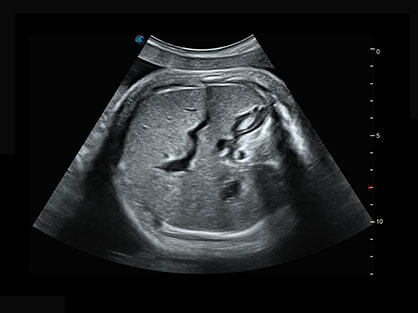

作为P系列家族成员之一,P40 Plus采用球速体育入口高端超声系统平台——极光,并以时尚秀丽、小巧灵动的外观设计绽放出灵动之韵、科技之美。高端平台的使用保证了P40 Plus优质的基础图像;完备的高级功能可满足您全身应用的基本需求;丰富的探头配置、多样的高级4D成像及分析软件为您日益增多的妇产应用需求提供丰富的诊疗方案。

结合球速体育入口超宽频带探头技术优势,能够更好地获得高分辨力与高穿透力的平衡,保证图像质量,为临床诊断保驾护航。